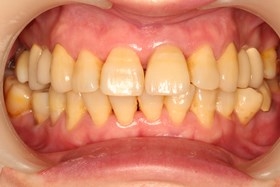

半年後假牙完成全口X光片、口內正面照片。

假牙完成後,門牙特寫、切端特寫照,暴牙已不復見